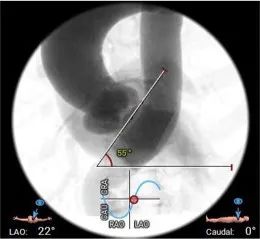

• 非横位心,升主无明显扩张,弓部宽度角度可,应用TaurusElite 输送器可顺利过弓、跨瓣;弓顶部存在钙化,小心通过防止钙化脱落

输送器顺利过弓跨瓣

工作位多角度评估瓣膜形态,位置理想